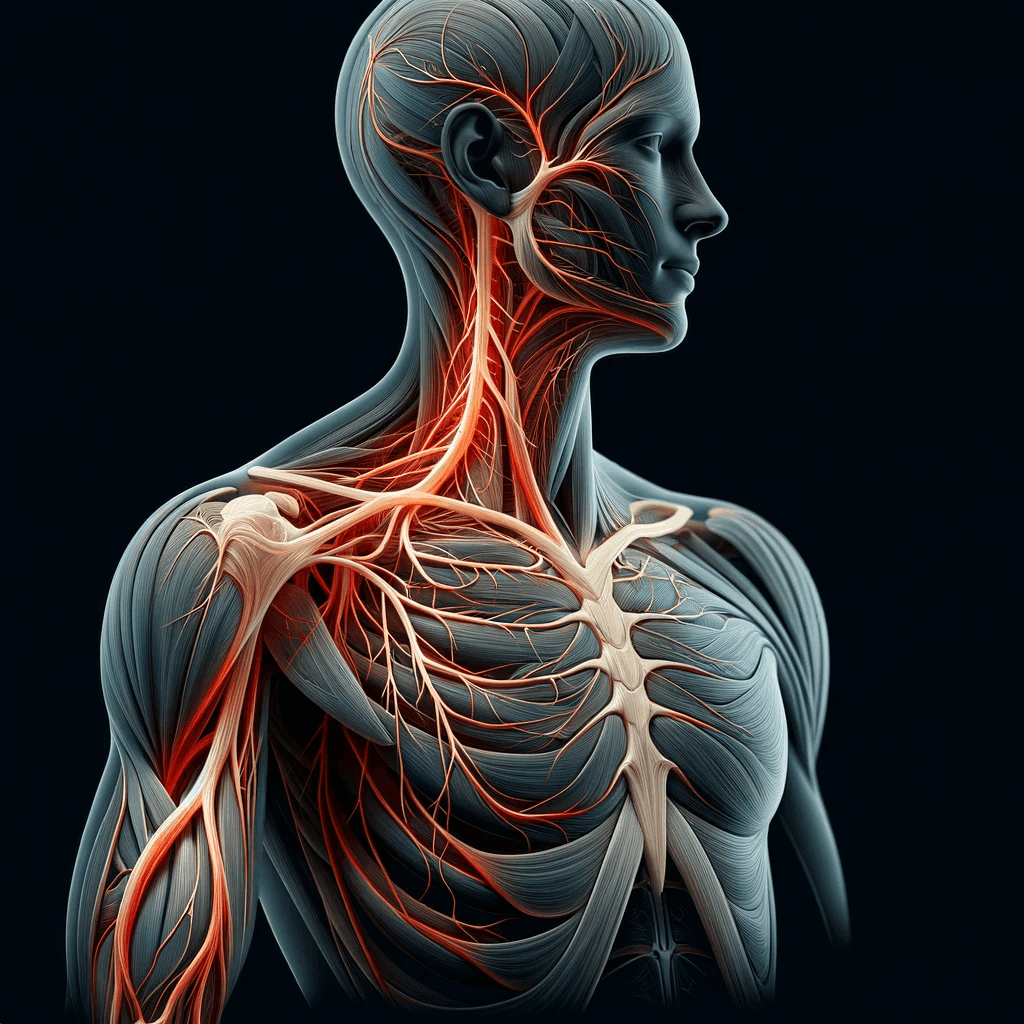

The cervical spine, a marvel of flexibility and support, consists of seven vertebrae, with the C5-C6 segment being particularly noteworthy.

This segment, located in the lower part of the neck, plays a pivotal role in supporting the head and enabling a wide range of motion.

However, its very functionality makes it vulnerable.

The C5-C6 disc, sandwiched between the fifth and sixth cervical vertebrae, is responsible for cushioning these bones and facilitating movement.

When this disc herniates, it means the inner gel-like substance breaks through its tougher exterior, potentially causing nerve irritation or compression.

Symptoms of a herniated disc at C5-C6 can vary, but they often include a distinct pattern of discomfort and physical limitations.

Patients may experience pain radiating from the neck down to the shoulder, arm, and even into the fingers, typically on one side of the body.

This pain can be accompanied by numbness, tingling, or weakness in the affected arm and hand.

In some cases, individuals might notice a decrease in their reflexes.

The susceptibility of the C5-C6 disc to injury is not just a matter of its location.

This segment endures significant stress due to its role in supporting the head and facilitating neck movements.

Repetitive motions, poor posture, and the natural aging process can all contribute to the wear and tear of this disc.

Additionally, traumatic events like falls or car accidents can cause sudden and severe damage.

Understanding these risk factors is crucial in both preventing and managing a herniated disc at C5-C6, setting the stage for effective treatment and long-term spinal health.